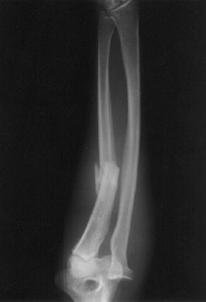

Fracturi simple: SPIRALA OBLICA TRANSVERSALA

Fractura spirala de Fractura transversa de diafiza femurala Fractura spirala de diafiza tibiala

diafiza humerala

Fractura spirala de diafiza tibiala Fractura oblica de diafiza tibiala Fractura transversala de diafiza tibiala